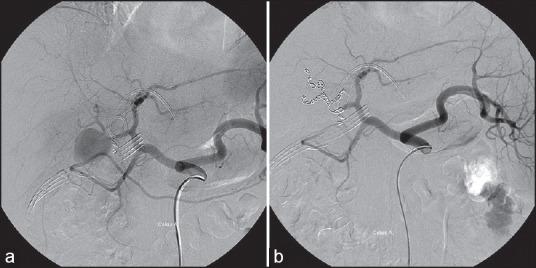

A hepatic artery pseudoaneurysm is a rare, but a potentially life-threatening complication after laparoscopic cholecystectomy (LC). Obstructive jaundice owing to a hepatic artery pseudoaneurysm after LC has never been reported. We report a patient with a hepatic artery pseudoaneurysm after LC who presented with tarry stools, bloody drainage and obstructive jaundice.